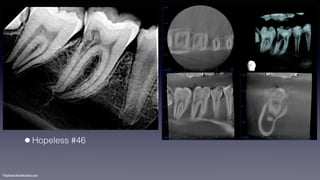

•Internal root resorption of #46

©sylvainchamberland.com

•Hopeless #46